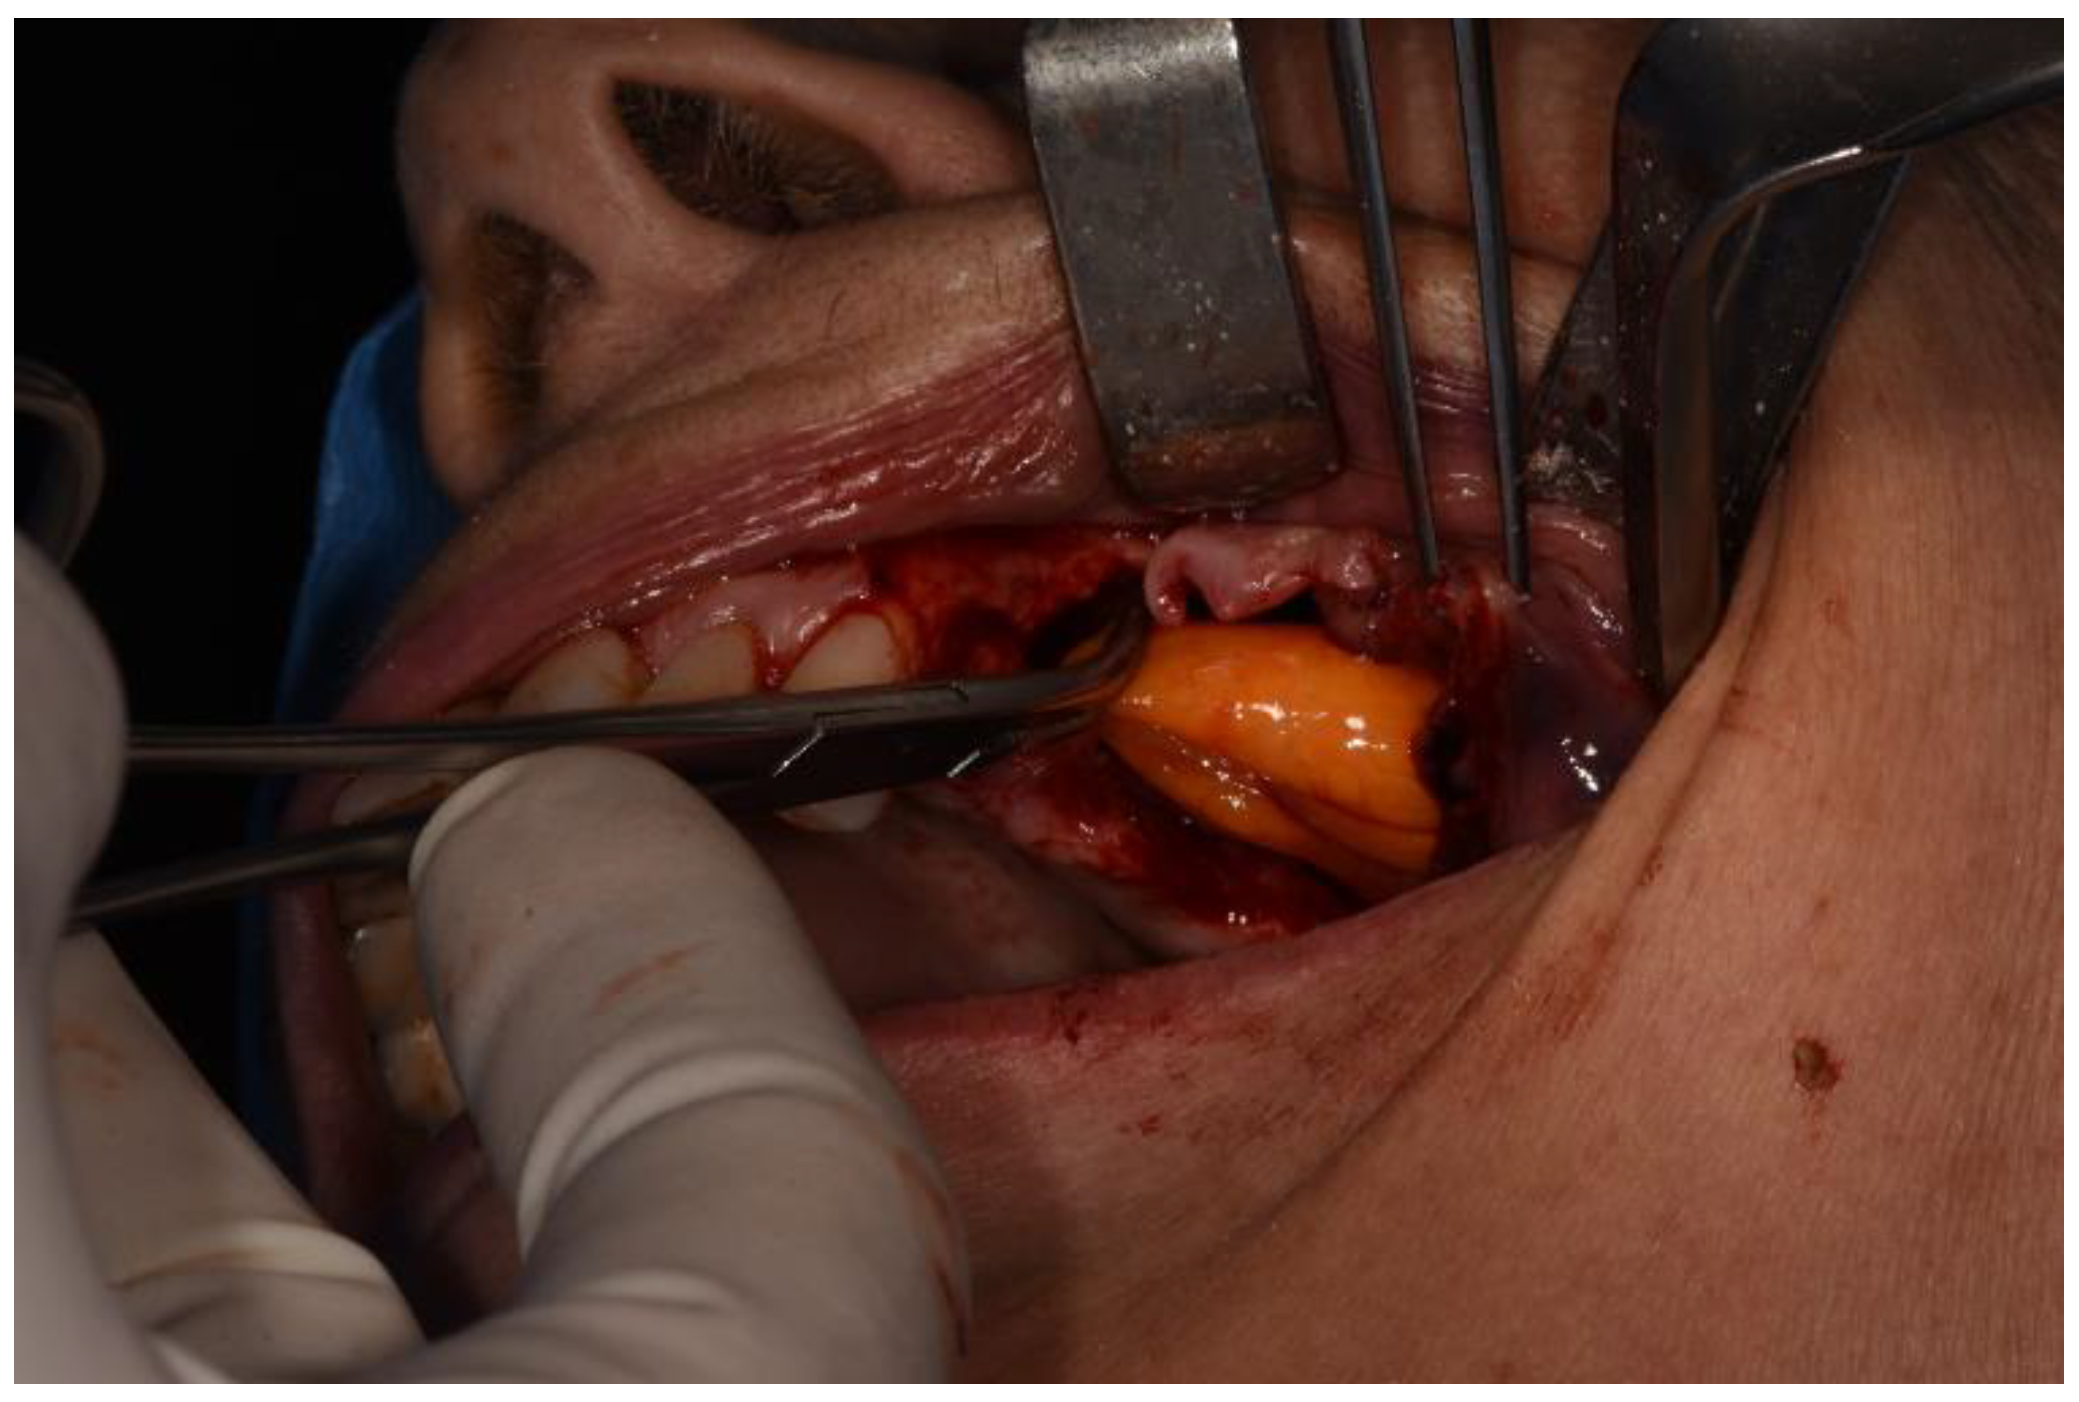

Figure 4. Osteotomy with piezoelectric device.